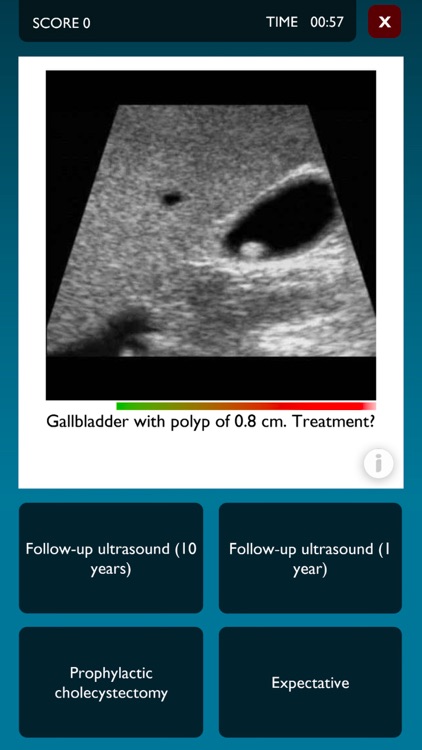

At the core of Medialis is a quick-fire quiz which challenges the player to respond quickly and correctly to medical dilemmas as presented in photos taken from the daily medical practice. It's a race against time. For each correct answer, time is added, while the player loses time for each incorrect answer. The aim is to answer as many questions correctly in the available time as possible.

This first version, which was created together with surgeons and anesthesiologists of the Academic Medical Center Amsterdam, covers the subjects of surgical mastery for laparoscopic cholecystectomy (surgery) and airway management (anesthesiology). Medical professionals are invited to submit their own questions for future updates. The developers are also interested in your suggestions and collaborations with other content partners / health care professionals.